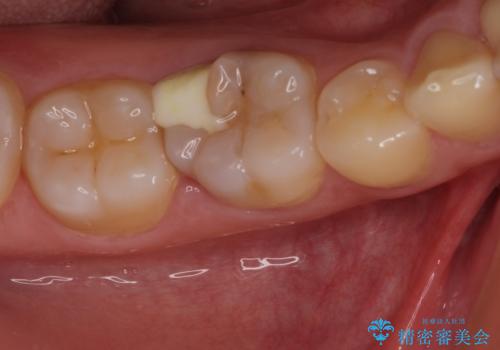

- 下顎左右奥歯に虫歯で痛みを感じるとのことで来院された患者様です。

むし歯が大きく、神経を取り除く可能性があることを理解いただいた上で虫歯を取り除き、その後はオールセラミッククラウンにて補綴することとしました。